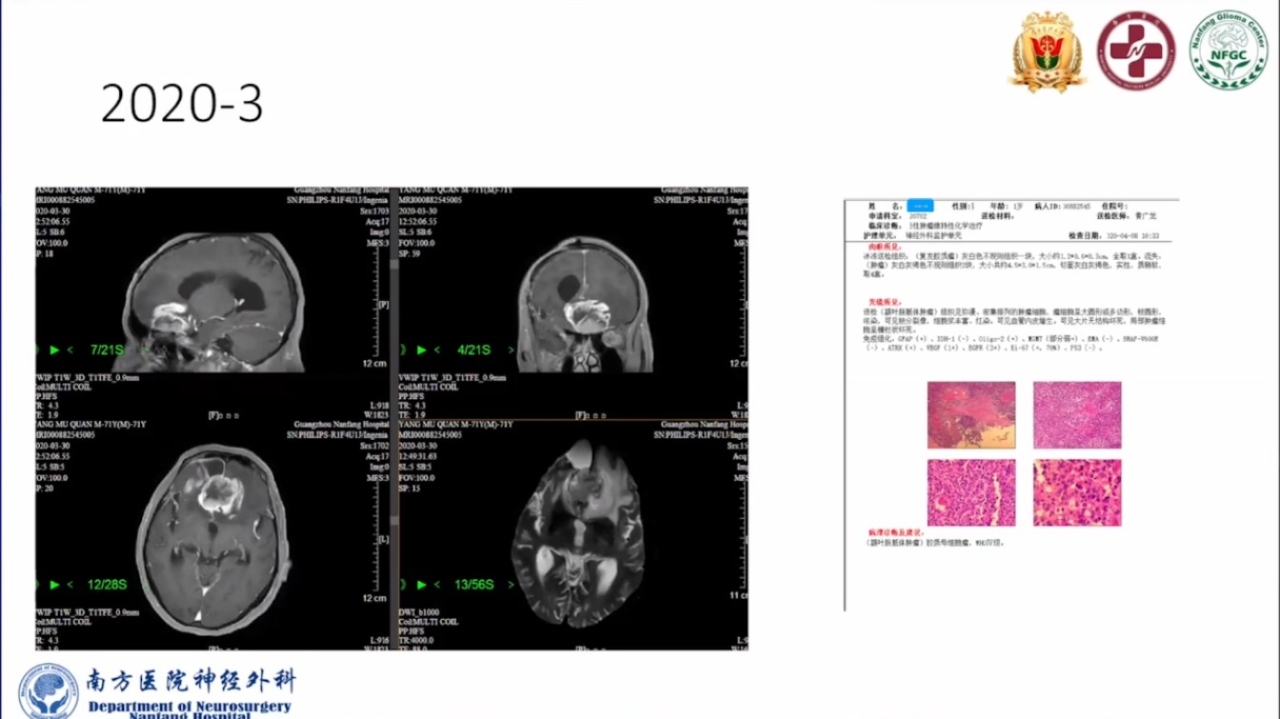

巨大的脑胶质瘤往往破坏皮层功能,推挤白质纤维束,包裹重要供血动脉,正常解剖结构移位。手术切除病变可以挽救患者生命。如果术中确保重要动脉不损伤,并在术前纤维束成像指导下按照解剖结构标志尽可能保留神经纤维束,患者将在获得辅助治疗机会的同时,神经功能也得以逐步恢复,更有利于脑胶质瘤的预后。

会议内容截图